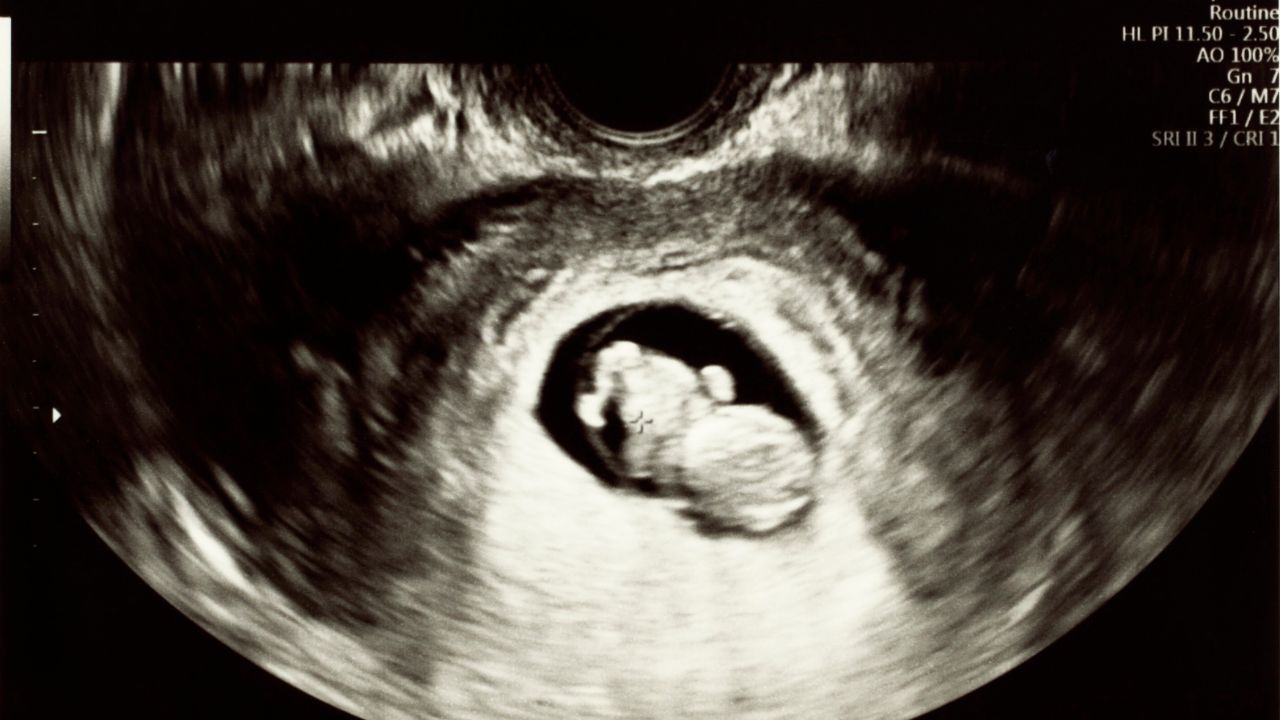

A partir de esta semana 6 de embarazo, es posible detectar el latido cardíaco mediante ecografía transvaginal y escucharlo utilizando la tecnología Doppler. Este momento representa un punto de especial importancia tanto para los médicos como para los padres, ya que permite confirmar el desarrollo adecuado del embrión y detectar posibles anomalías cardiacas tempranas.

En esta etapa, la ecografía transvaginal de alta resolución puede identificar claramente las estructuras cardiacas, lo que permite a especialistas detectar posibles defectos congénitos del corazón. El diagnóstico temprano de cardiopatías congénitas es fundamental para planificar el manejo perinatal y las intervenciones necesarias.